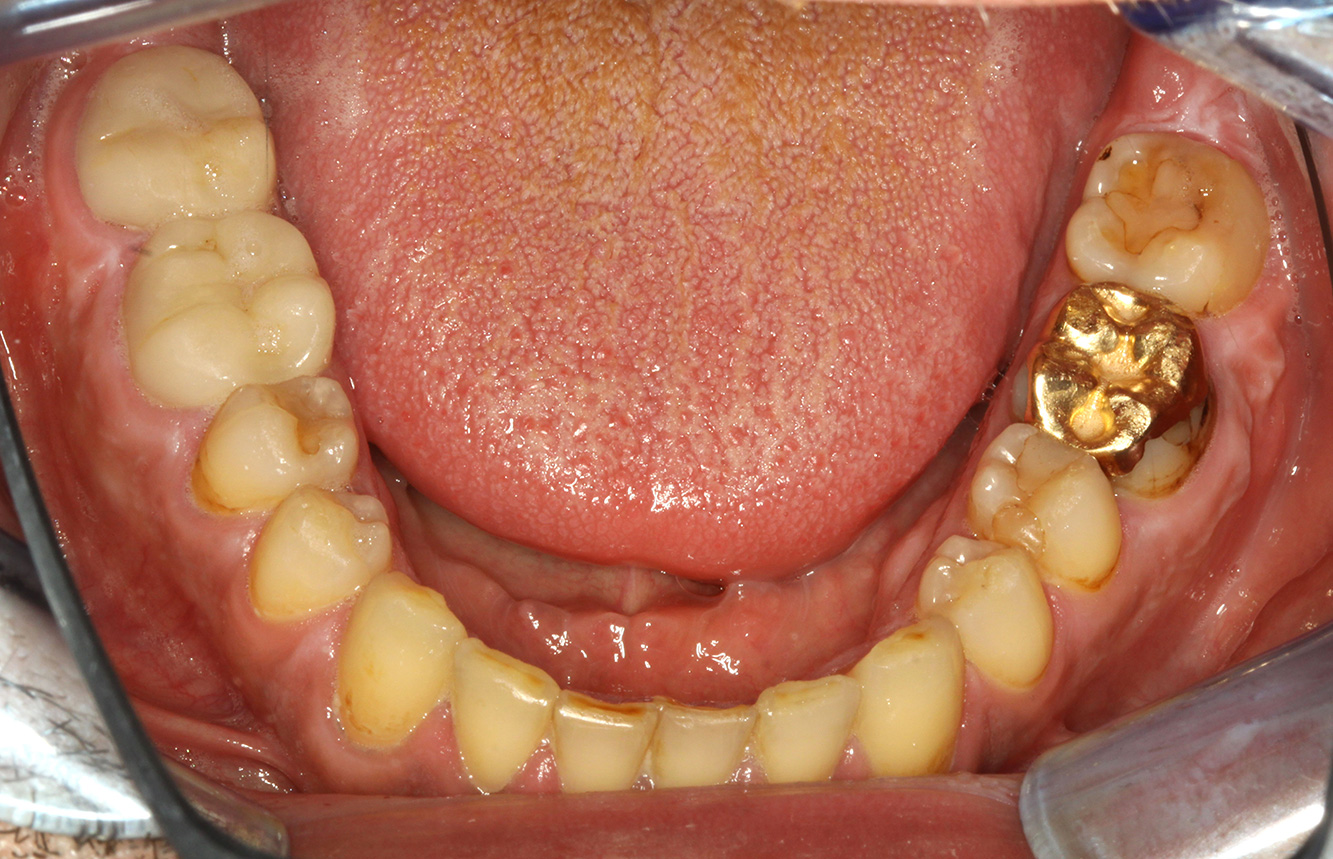

The endocarditis patient with active caries lesions*

The patient is 39 years old and has previously undergone aortic valve replacement due to valve failure and endocarditis. ASS 100 is taken regularly as an anticoagulant. In terms of lifestyle, the patient’s diet is classified as caries-promoting due to the regular consumption of sugary foods and the fact that six to seven meals are consumed daily. The patient’s oral health indicates a moderate risk of caries, with active lesions. The risk of periodontitis is low, but gingivitis is present. The following recommendations are made for prophylactic treatment.